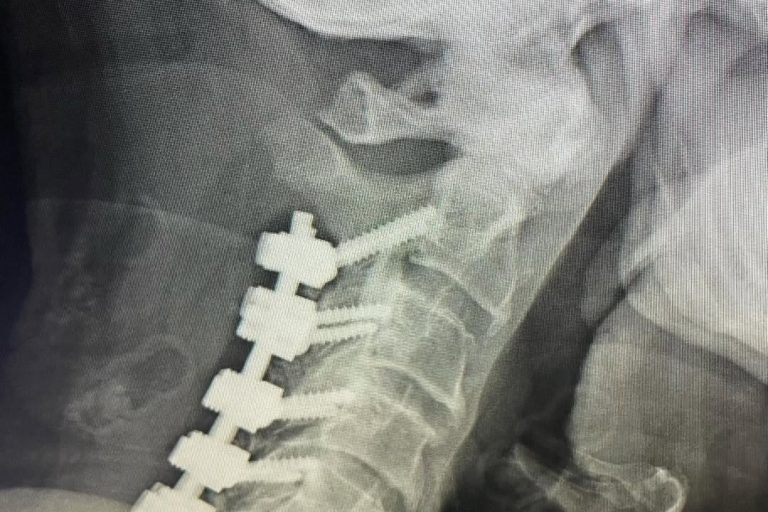

Meet Lin Sanders—a true inspiration of resilience and determination! Part 1 Lin underwent a complex two-level lumbar fusion at Texas Neuro-Spine Surgery. The procedure involved an anterior lumbar interbody fusion (ALIF) at L3-4 and L4-5, followed by laminectomies and pedicle screw instrumentation at the same levels. These surgeries were performed to help address her back…